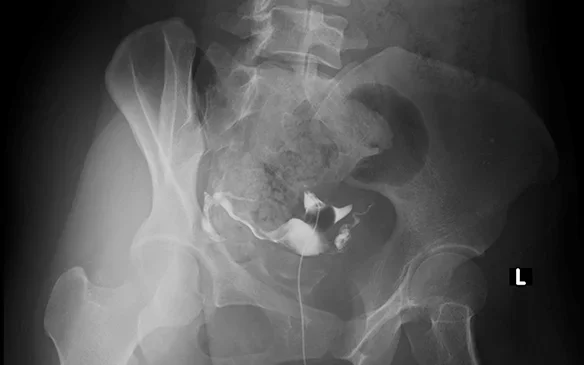

Radiografie uter si oviduct cu substanta de contrast

Histerosalpingografia este o investigatie imagistica destinata in principal femeilor cu probleme de fertilitate. Prin acesta metoda se poate explora intr-un mod indirect interiorul cavitatii uterine, precum si permeabilitatea trompelor uterine, contribuind la stabilirea cauzei infertilitatii.